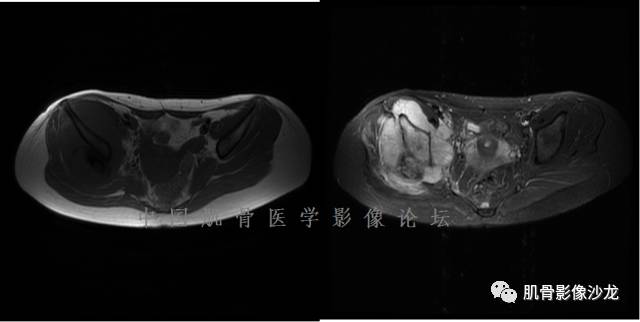

雪舞 :第二例,位于骶骨,有骨质破坏并有软组织肿块,软组织肿块边界清

雪舞: 第二例我们能够看到破坏与软组织肿块不成比例,软组织肿块大,破坏小

雪舞 :第二例挺难的,骨质破坏是溶骨性的,局部皮质中断,软组织肿块外缘光滑

雪舞 : 软骨肉瘤的发病率居原发性恶性骨肿瘤的第三位,其特点是肿瘤内具有软骨基质

雪舞:弓形钙化,钙化比例少于面积的1/3,钙化边缘模糊

雪舞 : 都是软骨肉瘤鉴别于内生软骨瘤有意义的区别点